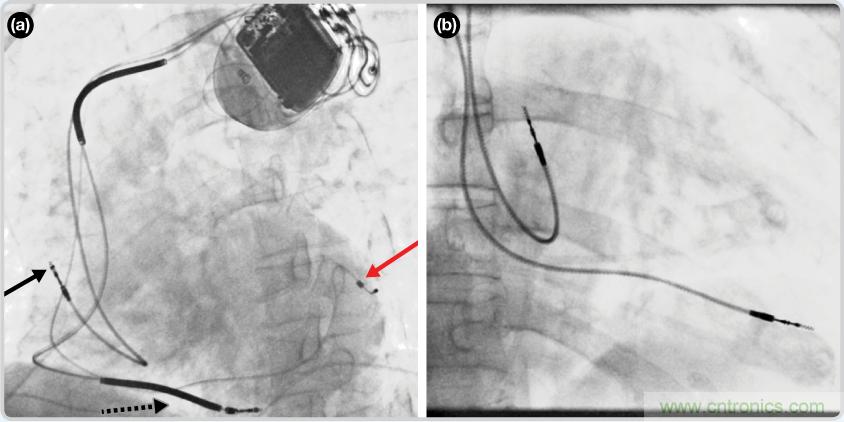

CRT器件在圖4(a)中的透視圖像中可以看見(jiàn)。醫(yī)師就是利用這種影像來(lái)放置導(dǎo)聯(lián)線的。對(duì)于非專(zhuān)業(yè)人士來(lái)說(shuō),這種影像是很難解讀的??梢钥吹叫呐K淡淡的輪廓——這是搏動(dòng)中的心臟的靜態(tài)視圖。起搏器位于右心房上,心臟頂點(diǎn)指向右下方。在這個(gè)典型的導(dǎo)聯(lián)線放置實(shí)例中,黑色箭頭指向右心房導(dǎo)聯(lián)線。虛線黑色箭頭指向右心室導(dǎo)聯(lián)線。紅色箭頭標(biāo)示的導(dǎo)聯(lián)線只能看到一部分,這是左心室導(dǎo)聯(lián)線(紅箭頭指向電極尖端)。圖4(b)展示的是雙腔起搏器的典型導(dǎo)聯(lián)線放置透視圖像。右心房導(dǎo)聯(lián)線指向上方,置于右心房中。右心室導(dǎo)聯(lián)線則位于右心室頂部。

圖4. 起搏器導(dǎo)聯(lián)線放置的透視圖像3 (a). 單腔起搏器;(b).雙腔起搏器